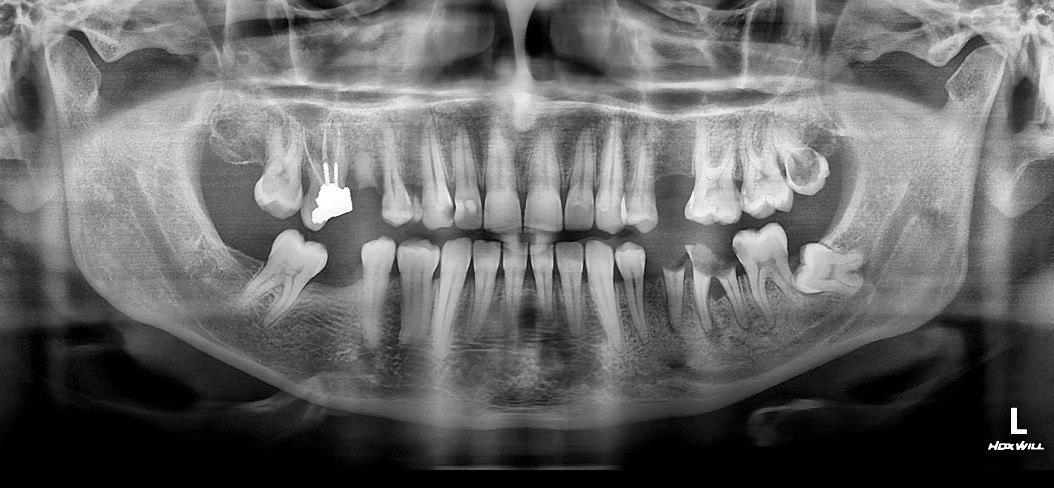

Panorex radiographs were used to demonstrates the number, position and growth of all the teeth including those that have not yet surfaced or erupted, to view the entire mandible and maxilla, to evaluate the condyles, to evaluate the connection between the jaws, to evaluate the connection between the lower wisdom teeth to the mandibular canal. OPG can also be used in cases where the patient is more than eighteen years old and no wisdom teeth can be seen in the mouth without a history of tooth pulling.

OPG has also been used in cases where there is a large number of caries and in cases where the patient is unable to open the mouth for intraoral radiography due to trismus. OPG can also be used before implanting multiple types of fixed prostheses, in cases of severe pain in the mouth for no apparent reason, in cases of posterior implants to examine the mandibular canal and maxillary sinus, and in cases of jaw’s trauma.